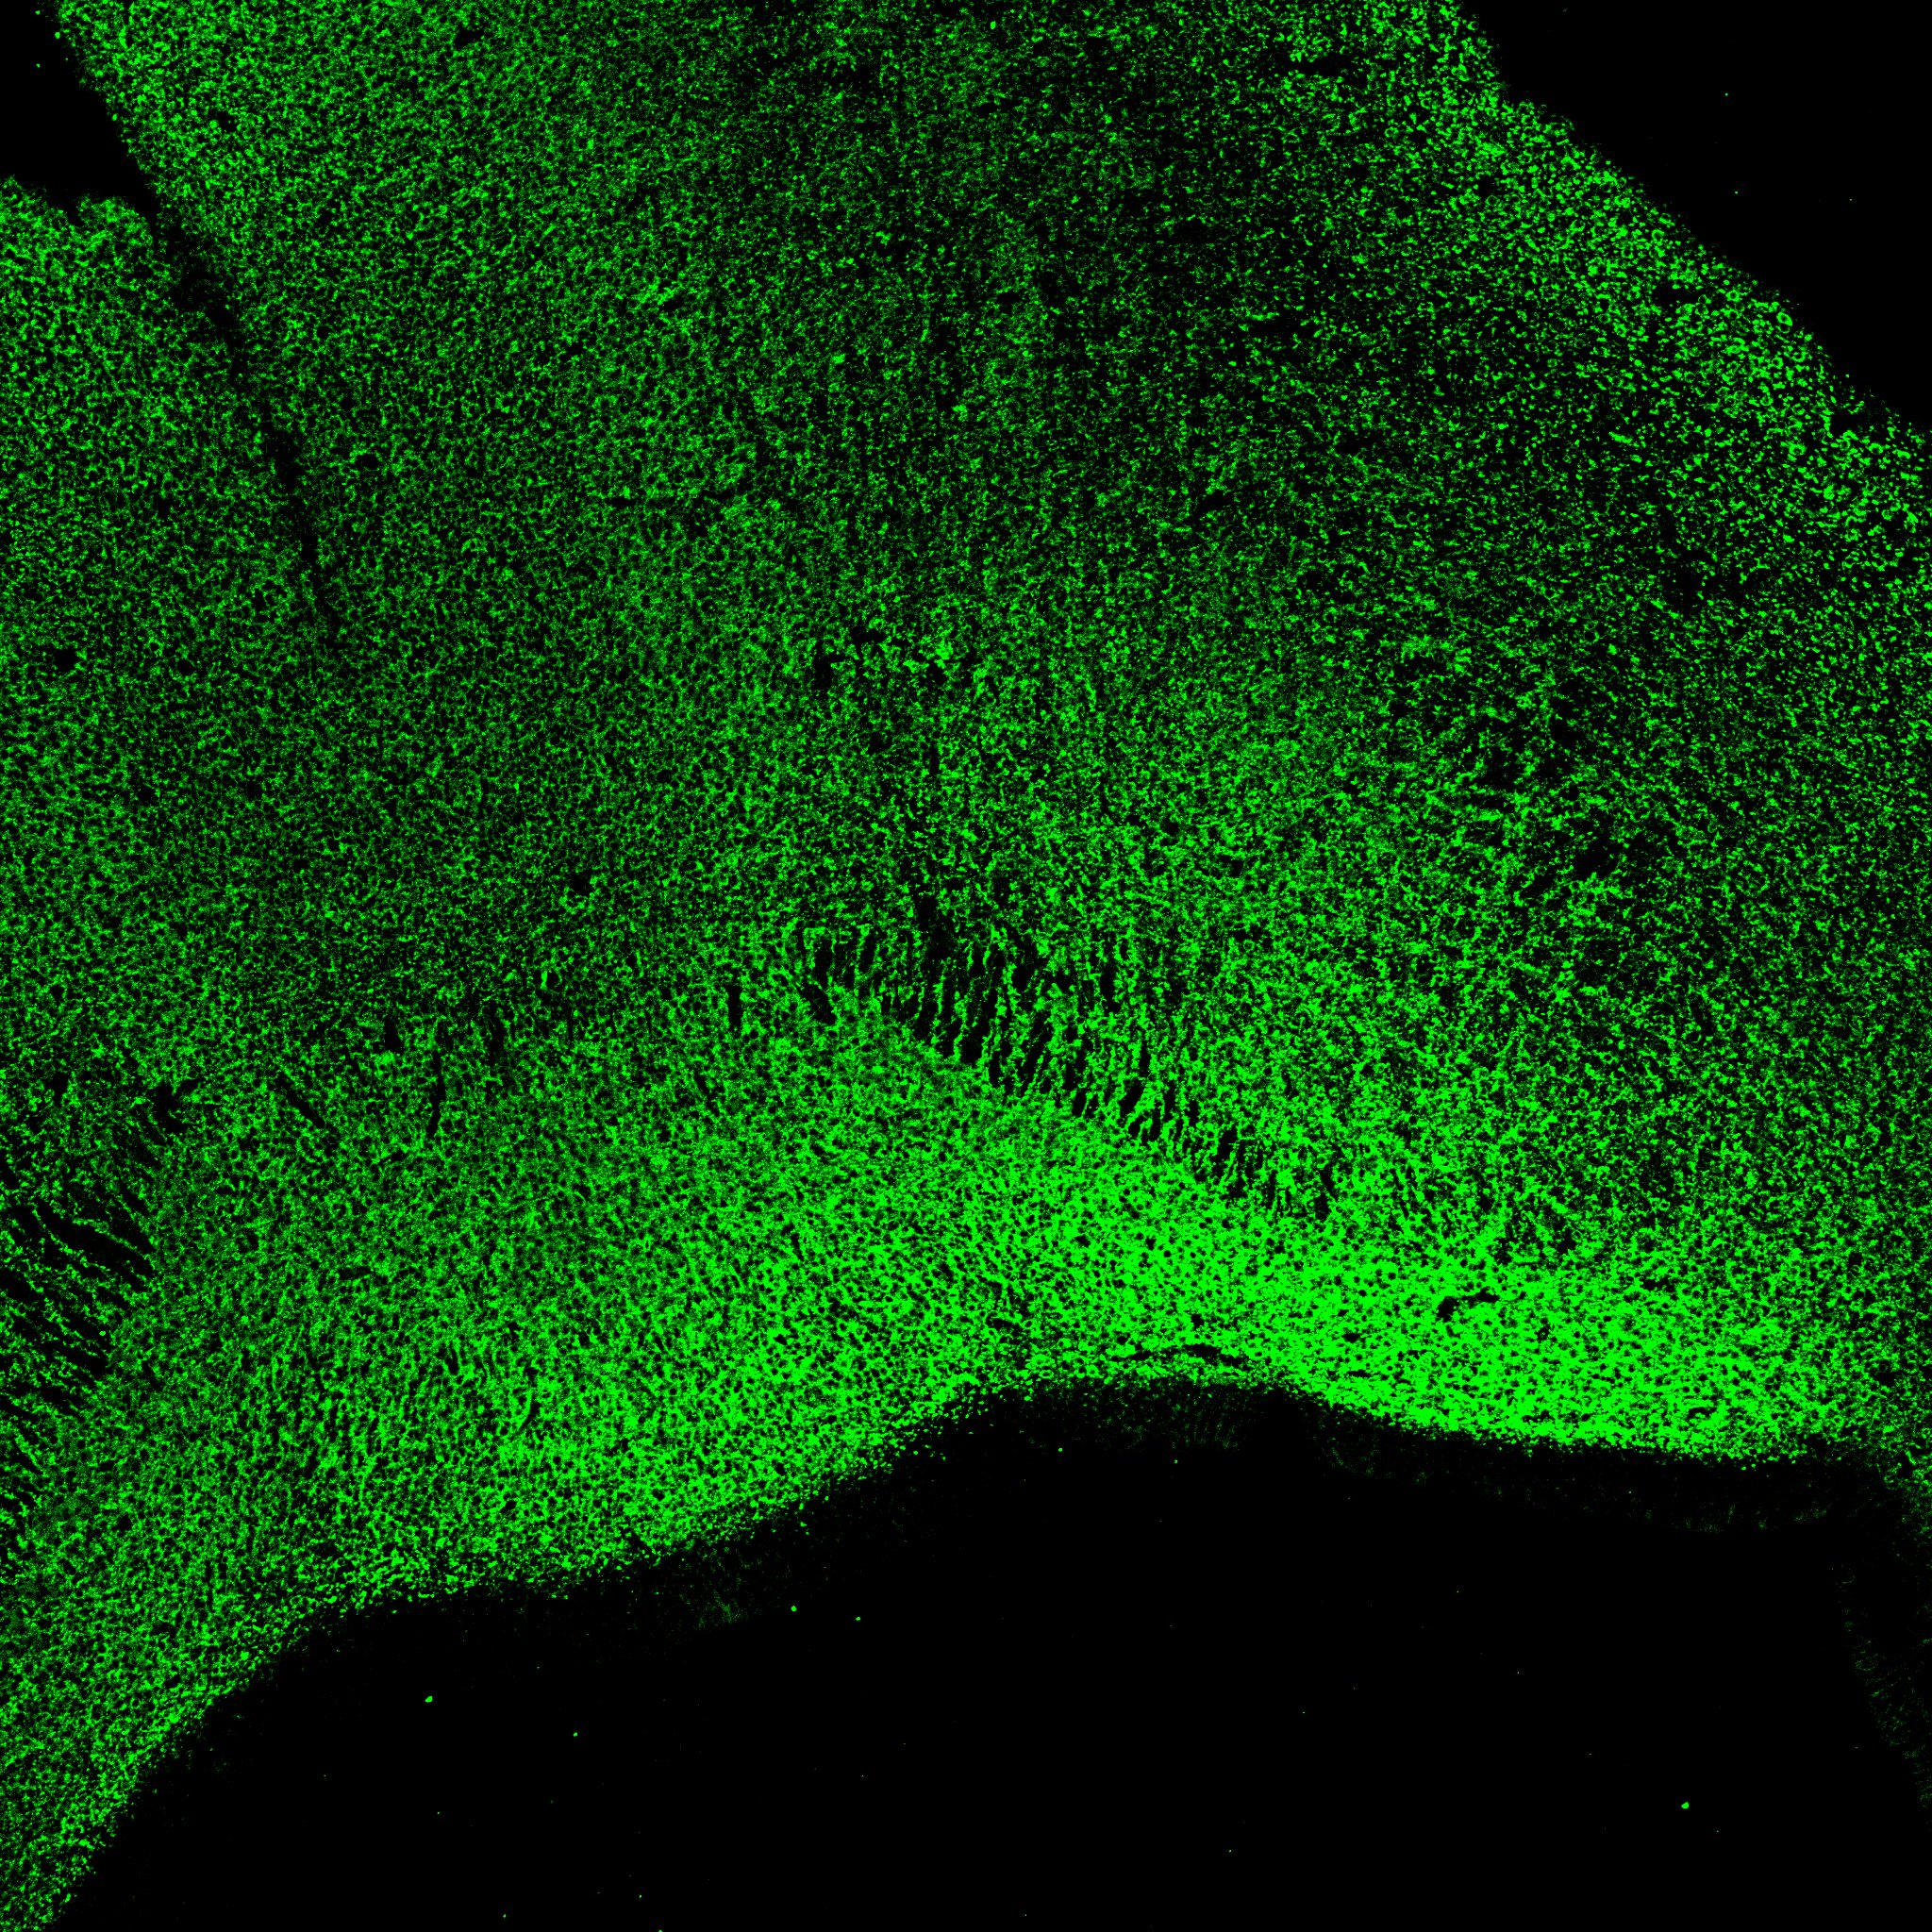

KI67

6PCW human midbrain